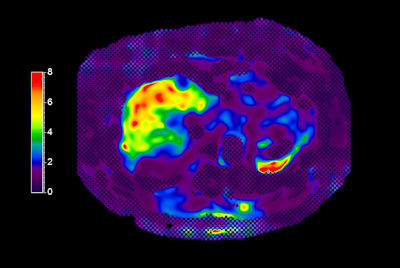

Liver quantification